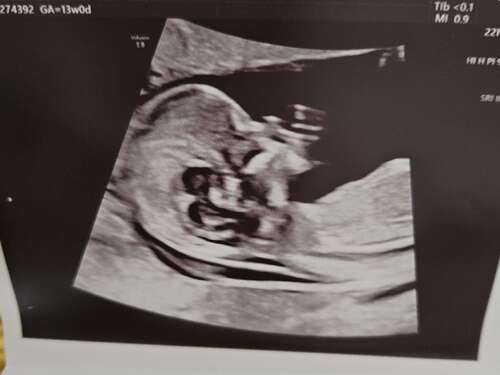

Bijna 16w, ik denk dat dit de mooiste echo is die ik tot nu toe heb gehad🥰 zijn mondje gwn😍🥰🥹